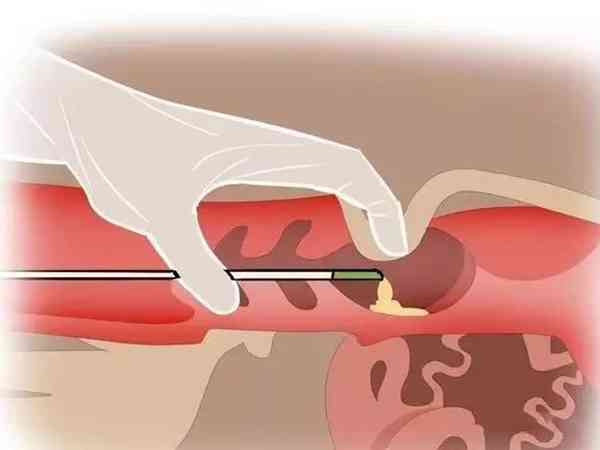

当患者的amh值为0.41的时候,做试管的成功率是并不高的,但是如果患者取到的卵子质量比较好,那么会对试管成功率有正面的影响的。因为患者在试管促排卵过程中得到的卵子质量比较好的话,会对患者做试管婴儿的成功率有一定影响的,会使试管的成功率有所提高,除了卵子数量以外,卵子质量也同样是影响试管婴儿成功率的关键因素之一。

性激素六项检查amh0.41储备功能差做试管婴儿的成功率并不高,但毕竟每个患者的身体情况不同,其成功率也是因人而异的。amh也称“抗缪勒管激素”,正常情况下女性的amh值应该在2-6.8ng/ml之间,当amh值低于正常数值时,则表示女性卵巢已经衰竭,卵泡储备少。但试管婴儿的成功率与卵泡的数量是没有关系的,理论上只要有一颗卵子,只要卵子质量好,就有可能成功。因此,amh0.41对试管婴儿成功率的影响不大,卵子质量好坏是影响试管婴儿成功率的关键因素。

AMH值越低则卵巢功能越差,当AMH值低于0.7ng/ml时,表示卵子库存量已严重不足,自然受孕的几率非常低。但如果卵子质量优质的话,试管婴儿成功率还是比较高的,因为卵子质量是决定试管婴儿成功率的关键因素。下面就说说amh只有0.41做试管如何进行挽救治疗,具体如下:

- 1. 由于女性的卵巢储备低amh只有0.41,因此获取空卵泡的几率非常大,所以在试管期间一定要在医生的指导下进行药物治疗,尽量让卵泡生长起来,只要有卵泡就还有希望取到卵子,使试管成功;

- 3. amh值0.41,只要amh值没有为“0”,那么就有卵泡存在的机会,做试管婴儿,理论上只要一颗卵子,就代表了一个新生命,抢救好每一颗卵子,这是试管治疗的基本原则,关键是个人的争取意愿。